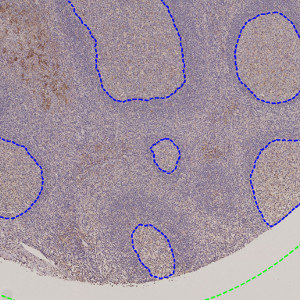

Outlined germinal centers (blue) on TMA core.

This APP automatically outlines germinal centers in tonsils stained for PD-L1 and is intended as an accessory APP to help isolate regions for further analysis.

Tonsil tissue may be used as positive/negative controls for PD-L1 staining. Because the PD-L1 expression varies significantly between the tissue compartments, it is of interest to differentiate between tissue regions before evaluating the PD-L1 expression.